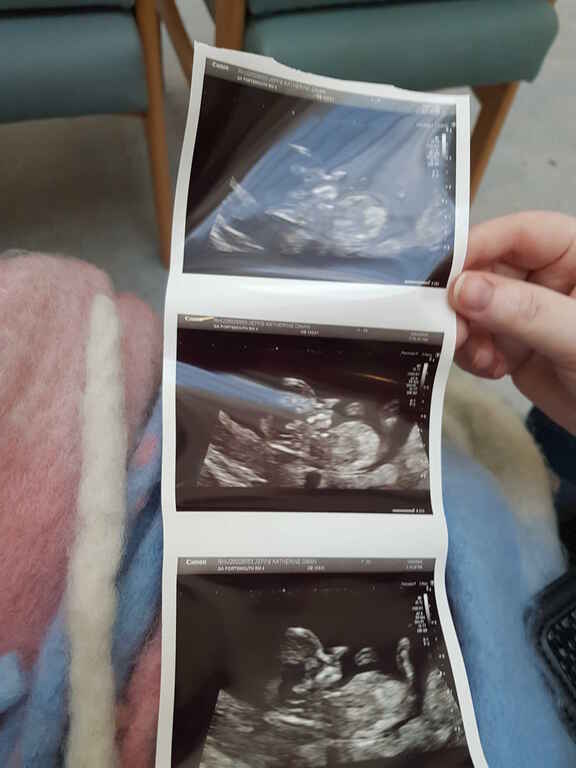

Photos 2024 January 21, 2024 · #photos#2024 « PreviousEmacs asynchronous copying using dired-async-mode Next »Opening Frequently Used Files More Efficiently using consult A new year, a new gallery! « PreviousEmacs asynchronous copying using dired-async-mode Next »Opening Frequently Used Files More Efficiently using consult